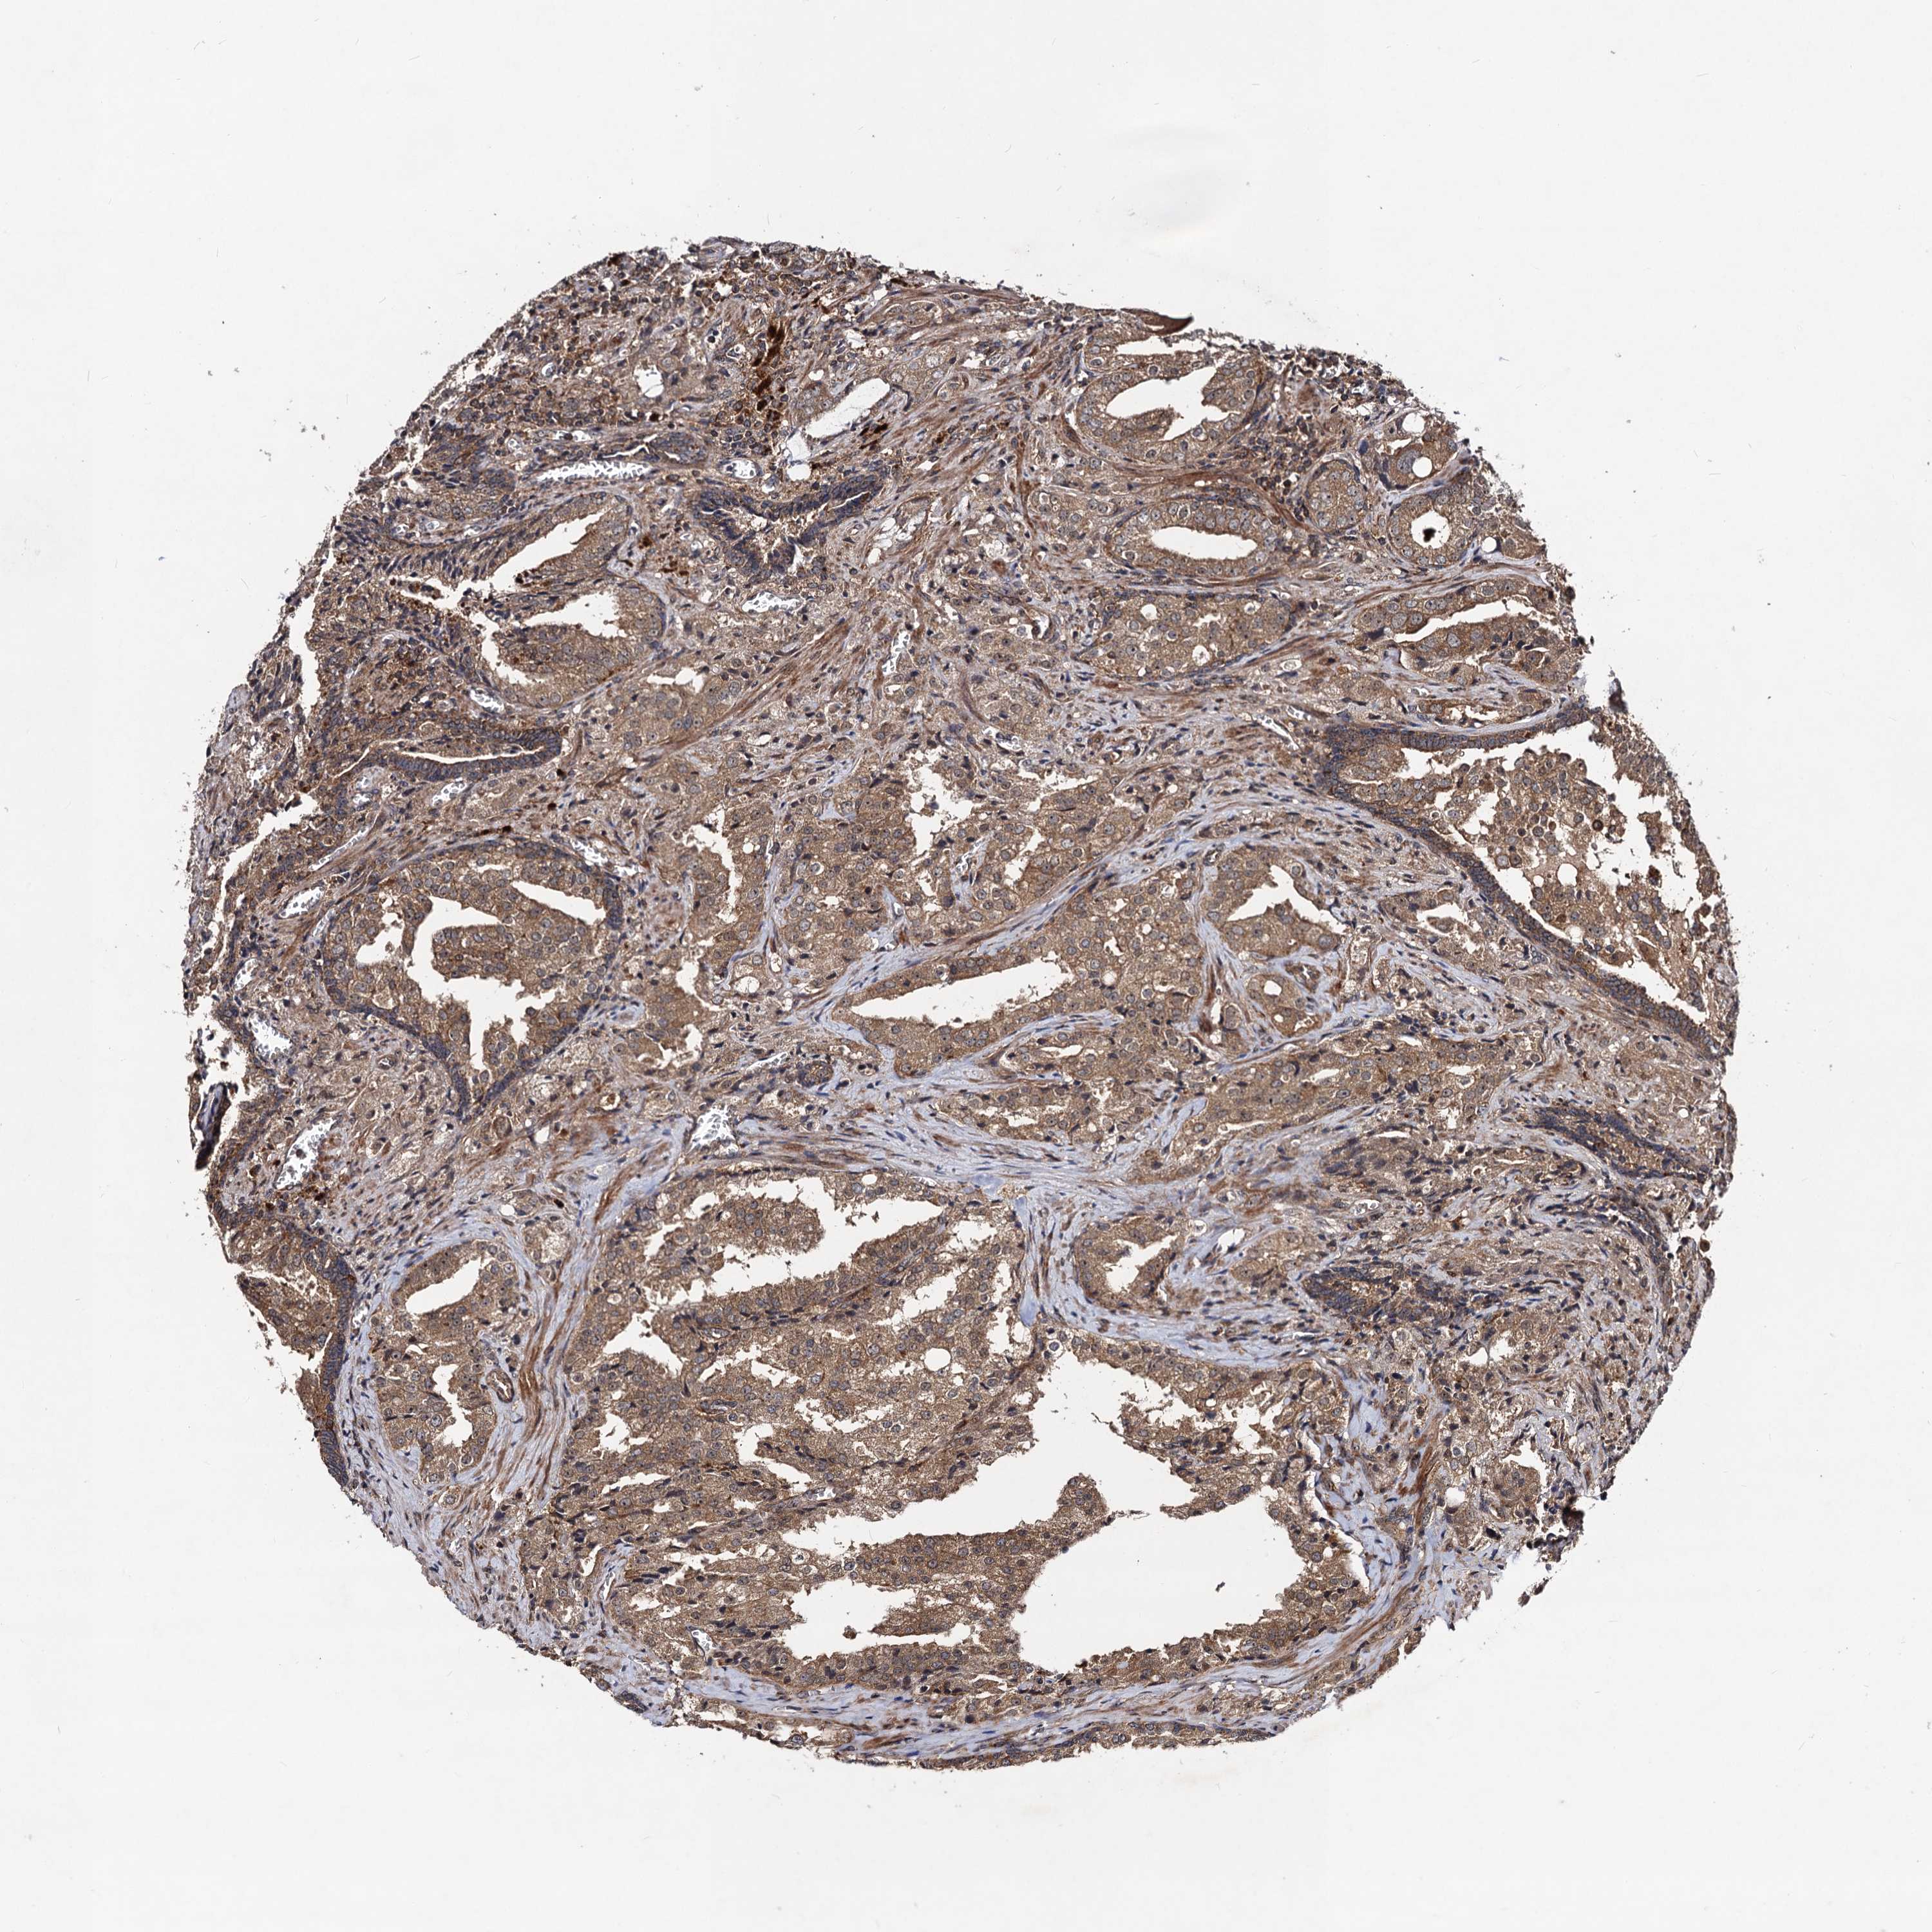

PROSTATE CANCER - Protein expressioni

A mouse-over function shows sample information and annotation data. Click on an image to view it in a full screen mode. Samples can be filtered based on level of antibody staining by selecting one or several of the following categories: high, medium, low and not detected. The assay and annotation is described here.

Antibody stainingi

Antibody staining in the annotated cell types in the current human tissue is reported as not detected, low, medium, or high, based on conventional immunohistochemistry profiling in selected tissues. This score is based on the combination of the staining intensity and fraction of stained cells.

Each image is clickable and will lead to virtual microscopy that enables deeper exploration of all samples and also displays staining intensity scores, fraction scores and subcellular localization as well as patient and tissue information for each sample.

Antibody HPA041507

Antibody HPA041599

Staining

High

Medium

Low

Not detected

Intensity

Strong

Moderate

Weak

Negative

Quantity

>75%

75%-25%

<25%

None

Location

Nuclear

Cytoplasmic/membranous

Cytoplasmic/membranous,nuclear

Adenocarcinoma, High grade

Adenocarcinoma, Low grade

Adenocarcinoma, NOS